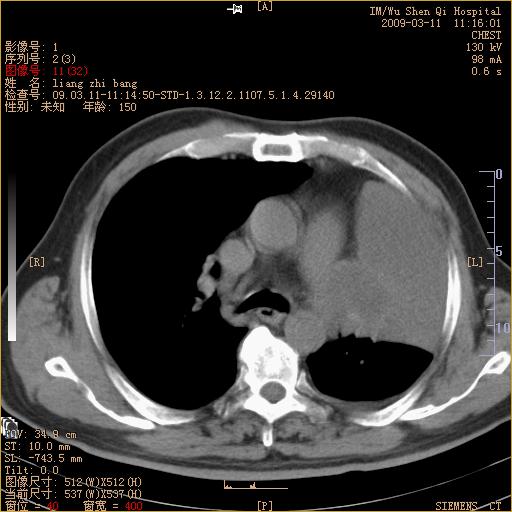

标题: CT18604:男,60岁,咳嗽一月余 [打印本页]

标题: CT18604:男,60岁,咳嗽一月余

1)考虑左肺上叶中央型肺癌并左肺上叶肺不张;建议必要时行纤支镜检查进一步明确诊断。2)左侧胸腔积液。

肺门肿块、支气管开口闭塞伴肺不张及胸水!典型的中心型肺癌变现!

1、左肺上叶中央型肺癌并上叶阻塞性肺不张。

2、左侧胸腔少量积液,右侧胸膜轻度增厚。

左肺们肿块并左肺上叶不张。考虑左肺中心性肺癌并左肺上叶不张及左侧胸腔积液